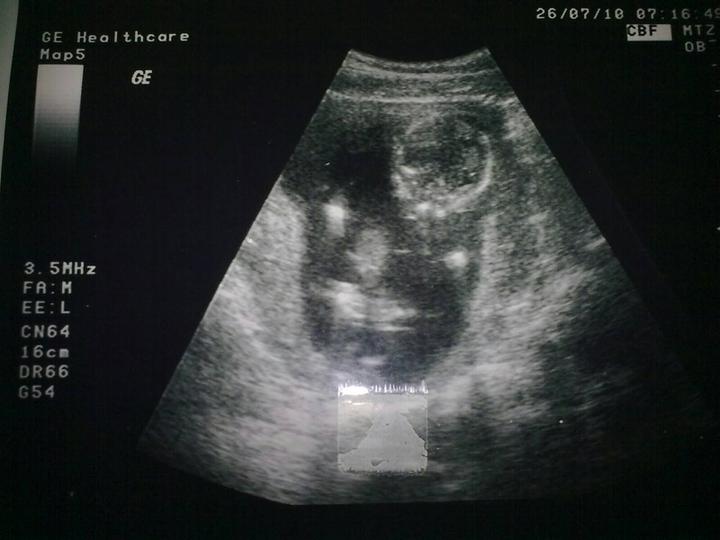

Dnes som videla moju pisulku, vazi 1390 gramov, ma kraaaaaaasne rucicky, nozicky, palceky, rebierka... :D